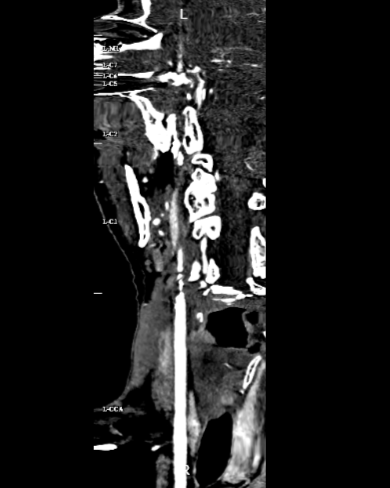

头颈部CTA提示左侧颈内动脉闭塞。

左侧颈总动脉造影可见颈内动脉闭塞,动脉末期可见颈外动脉经眼动脉向颈内动脉代偿,颈内动脉末端以远不显影。

在泥鳅导丝及5F MPA1造影管配合下将6F股动脉长鞘至于左侧颈总动脉行路图,在200cm Sur-reach®微导丝配合下将2.5*15mm颅内球囊扩张导管扩张后,将6F导管鞘通过颈内动脉起始部闭塞段,行路图可见颈内动脉颈段至海绵窦段后膝处血栓影,左侧大脑中动脉闭塞。